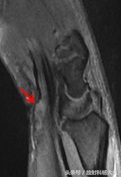

王女士的腕关节图像,质子相矢状位见屈肌支持带弯曲、正中神经突然增粗。

当出现类似症状时,MRI对腕管综合征的确诊有一定意义,横轴位图像最为典型,可以观察到正中神经的受压扁平,T2WI信号增高或增强扫描出现强化,屈肌支持带弯曲,腕骨和肌腱之间的脂肪间隙消失,和/或正中神经的直径突然改变。其中正中神经形态出现突然变化是最为特征性的变化。